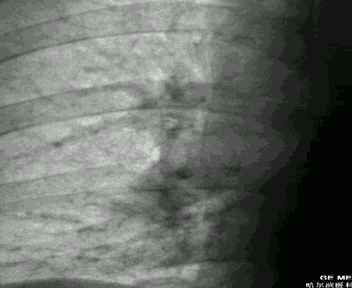

胸部X线片

两肺纹理稀疏,肺动脉段突出